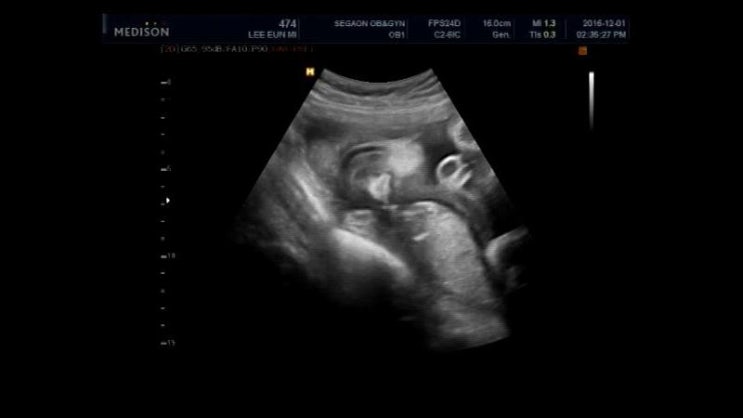

2016년 12월 1일 오복이 32주 6일차

오늘은 아빠 쉬는날이라 함께 오복이 만나고 온날~ 거의 33주차인데 오복이 2.5kg정도~ 오늘도 어김없이 의...